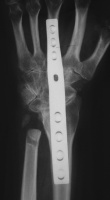

| She had progressive deterioration over two years with worsening pain and instability. |

| Eventually, she was treated with wrist fusion, distal ulnar resection and extensor carpi ulnaris tenodesis, and basal joint excision arthroplasty with split abductor pollicis longus anchovie interposition and ligament reconstruction - all through a single dorsal approach.: |